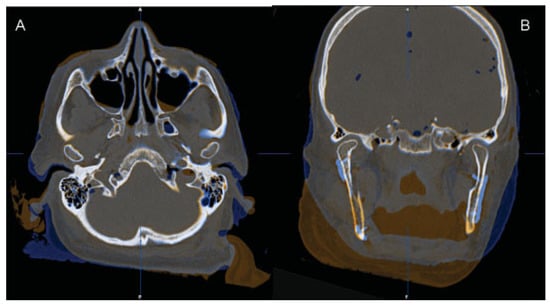

The fusion of preoperative and postoperative CT datasets showed that the positions of the two residual rami and condyles after the fixation of the CAD/CAM-fabricated reconstruction plate were almost identical to those before resection (Figure 10). We were thus able to transfer the virtually planned position of the patient-specific CAD/CAM-fabricated reconstruction plate precisely to the site of surgery. Accordingly, there was no dislocation of the residual bone segments (both rami and condyles).

The fusion of preoperative and postoperative CT datasets (Figure 10) demonstrates that an accurate positioning of the plate on the basis of planning is possible and that the dimensions of the mandible and the positions of the residual mandibular segments can thus be maintained. In our opinion, this plays an important role in maintaining or restoring temporomandibular joint (TMJ) function and occlusion in patients who still have occluding teeth after mandibular resection and reconstruction.

Figure 10. The fusion of preoperative (amber) and postoperative (blue) CT datasets demonstrated that the positions of the two residual rami and condyles after the fixation of the CAD/CAM-fabricated reconstruction plate were almost identical to those before resection. (A) Axial view. (B) Coronal view.